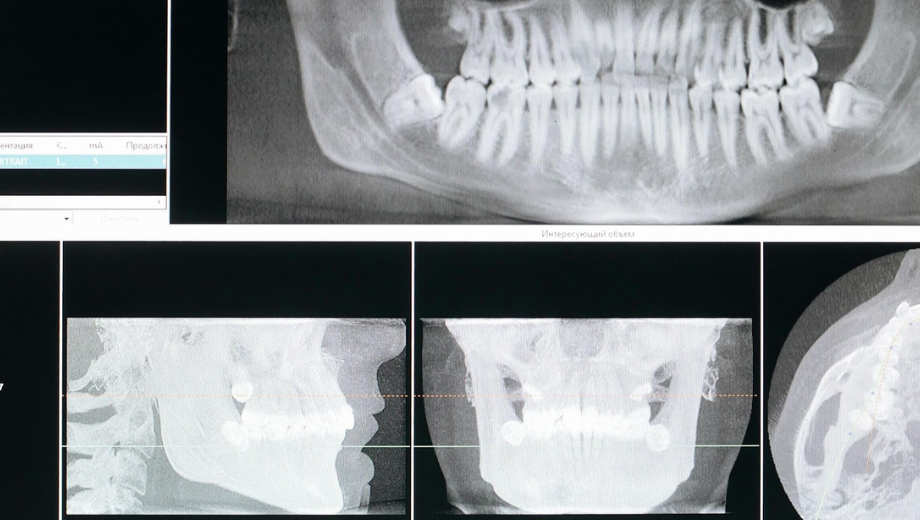

One of the first signs of tooth damage in children is often visible changes in color or texture. Teeth may develop white spots, indicating early enamel demineralization, or brown and black areas that suggest cavities forming beneath the surface. Rough or pitted enamel can signal that decay is beginning, even before pain appears. When damage progresses, pediatric dental crowns can be recommended to restore a tooth’s structure and protect it from further decay. Dental crowns help ensure the tooth remains functional and strong while preventing more invasive treatments later. Regular observation and dental checkups are key.